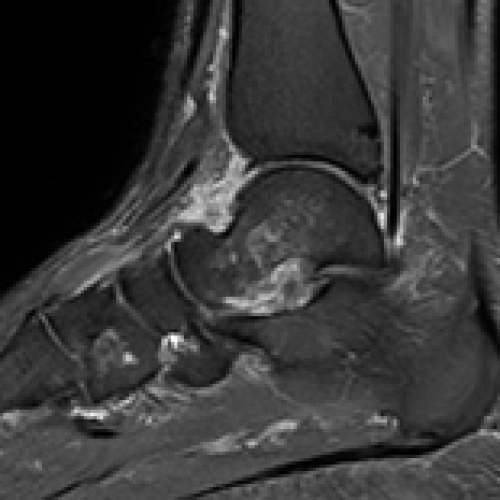

10 Nov 2024 : Clinical Research

Clinical Outcomes of Talus Bone Marrow Edema: Comparing Plaster Cast, Crutches, and Walking Boot Treatments

Muhammed Taha Demir

, Yigit Kultur

DOI: 10.12659/MSM.946072

Med Sci Monit 2024; 30:e946072